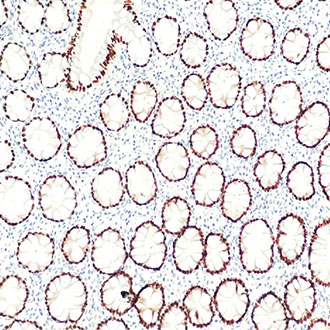

CDX-2

CDX-2 -